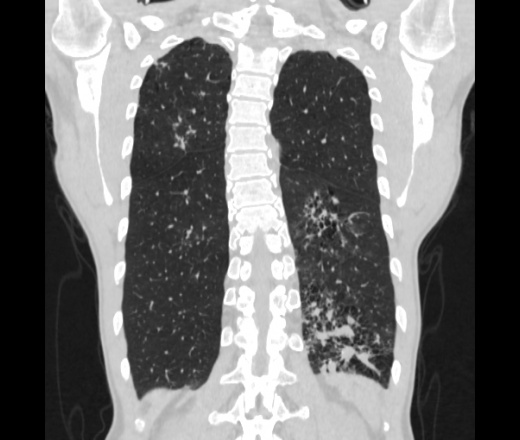

Мужчина пенсионного возраста. Цель назначения КТ ислючение зла в левом легком. Вижу тракционные бронхоэктазы с рубцовой эмфиземой по периферии, скорее всего БЭБ в стадии обострения. Дивертикулы трахеи. Выложил из за того что есть доля сомнения в отношении исключения зно3, немного смущают линии похожие на Керли.

Единственно, не сказал бы, что это тракционные бронхоэктазы, ну, и про линии Керли не вполне понял.

Ну да. Выразился не правильно. На фоне легочного рисунка усиленного линии похожие на септальные, не знаю как называются, при интерстиц.отеке похожие

На мой взгляд, это не главное, указал бы в описании - локально утолщен междольковый интерстиций, и всё